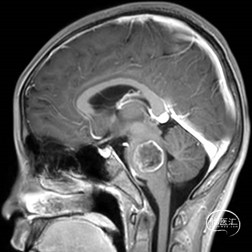

术后MRI

术前MRI